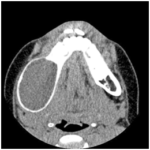

Ἡ διάγνωση σὲ ἀρχικὸ στάδιο θὰ προσεγγισθεῖ μέσω πανοραμικῆς ἀκτινογραφίας (εἰκ. 1) καὶ CT (ἡ εἰκ.2 ἔχει ληφθεῖ ἀπὸ τὴν βιβλιογραφία), ἐνῶ ἡ τελικὴ διάγνωση τίθεται μόνον διὰ τῆς βιοψίας. Ἡ θεραπεία εἶναι μόνον χειρουργικὴ καὶ συνίσταται στὴν ἐκτομὴ τοῦ ὄγκου καὶ ταυτόχρονη (ἀναλόγως τῆς θέσεως καὶ ἐπεκτάσεως τοῦ νεοπλάσματος) ἀνακατασκευὴ τῆς γνάθου, μὲ τοποθέτηση εἰδικῆς προθέσεως, συνήθως ἀπὸ κεραμικὸ ὑλικὸ.

Ἡ πανοραμικὴ ἀκτινογραφία τὴν ὁποῖα διενεργήσαμε (εἰκ. 1), ἔδειξε, πλησίον τῆς γωνίας τῆς κάτω γνάθου ΑΡ, κυστικὸ μόρφωμα, μὲ σαφῆ ὅρια (ἐξαιρουμένης μόνον τῆς ἔξω παρυφῆς του πρὸς τὸν σύστοιχο κλάδο τῆς κάτω γνάθου), ὅπου ὑπῆρχε μόλις ὑποσημαινόμενη ἀσαφοποίηση, ἡ δὲ παρυφὴ τοῦ κυστικοῦ μορφώματος ἐδῶ προσελάμβανε τὴν μορφὴ δίκην «γιρλάντας», τὸ δὲ ἐνδοκυστικὸ μέρος τοῦ τοιχώματος, κατὰ τὴν ἔξω καὶ κάτω παρυφὴ του, ἐνεφάνιζε ἀνώμαλες ὀστικὲς προσεκβολές, ἐναλασσόμενες μὲ διαυγαστικὲς μικρὲς ἑστίες, εἰκόνα προσομοιάζουσα μὲ τὴν ἀντίστοιχη δίκην «μελισσοκηρήθρας ἢ μωσαϊκοῦ». Στὸ κυστικὸ μόρφωμα δὲν ἐνυπῆρχαν ἔγκλειστοι ὀδόντες. Ἡ διαφορικὴ διάγνωση δὲν ἦταν εὔκολη γιὰ ἐμᾶς, διότι ἔπρεπε νὰ ἀναφέρουμε σειρὰ παθήσεων ποὺ προκαλοῦν παρόμοια ἀκτινολογικὰ εὑρήματα. Συμπεριλάβαμε λοιπὸν πέραν τοῦ ἀμελοβλαστώματος, τὴν μονοοστικὴ ἰνώδη δυσπλασία, τὴν θυλακιώδη κύστη, τὴν κερατινοκύστη, τὸ ὀδοντογενὲς μύξωμα καὶ τὸ ἠωσινόφιλο κοκκίωμα.